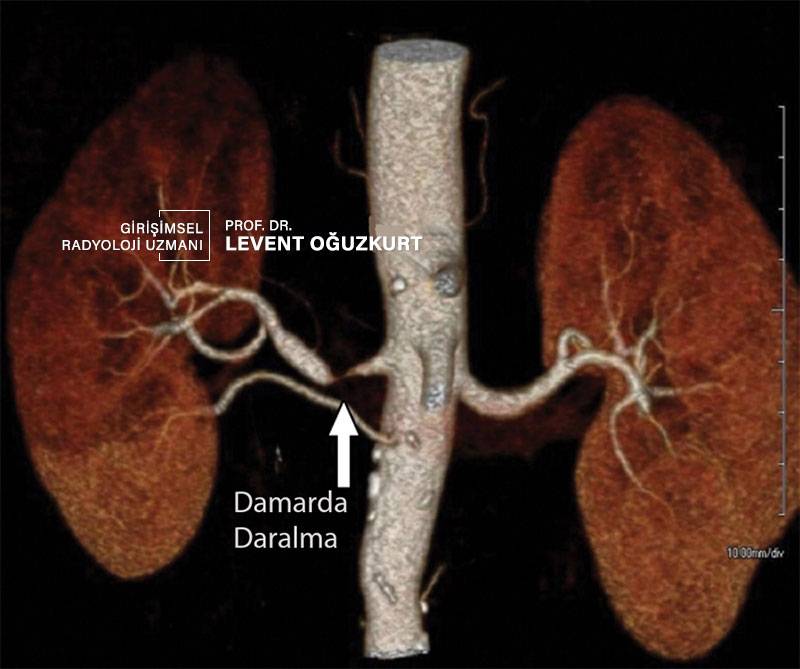

Böbrek damar tıkanıklığı (renal arter stenozu)

Halk arasında böbrek damar tıkanıklığı olarak geçse de böbrek damarlarında sıklıkla gördüğümüz ve tedavi ettiğimiz durum böbrek damarlarında tam tıkanma olmadan sadece daralma olmasıdır. Buna renal arter stenozu adı verilir.

Damarda daralma ya da tıkanıklık bir çok atardamar hastalığında olduğu gibi damar sertliği ya da damar kireçlenmesine bağlıdır. Bu tıkanıklık ya da daralma bazen hiç bir sorun yaratmaz ve tedavi gerektirmez. Bazı durumlarda ise tedavi gerekir.

Renal arter stenozu ne zaman tedavi edilmelidir?

- Damardaki darlık böbrek fonksiyonlarını kötüleştiriyor ise yani üre ya da kreatinin seviyesinde yükselme varsa

- Hastanın hipertansiyonu varsa ve 3 ilaç kullanmasına rağmen kontrol edilemiyorsa

- Hastanın hipertansiyonu varsa ve sistolik yani büyük tansiyon 20 mmHg üstüne çıkıyorsa

- Hipertansiyon varsa ve son dönmede daha kötüleşti ya da yükseldi ise

- Hipertansiyon genç yaşta ortaya çıktı ise (20-40 yaş arası)

Bu durumlara renovasküler hipertansiyon adı verilir. Yani hipertansiyonun sebebi muhtemel böbrek damar daralması ya da tıkanmasıdır. Ancak bu tüm hipertansiyonlu hastaların %2 si kadardır. Bu nedenle her hipertansiyonu olan kişide damarda sorun bulunursa tedavi gerekmez.

Renal arter stenozuna stent tedavisi

Böbrek damar darlığında en sık kullanılan tedavi yöntemi anjiyografi ile tedavidir. Bu tedavi vücudun diğer bölgelerinde yapılan stent tedavileri ile hemen hemen aynıdır. Bu nedenle anjiyografi ile damar darlık ve tıkanmalarının tedavisi bölümündeki bilgilere başvurabilirsiniz.